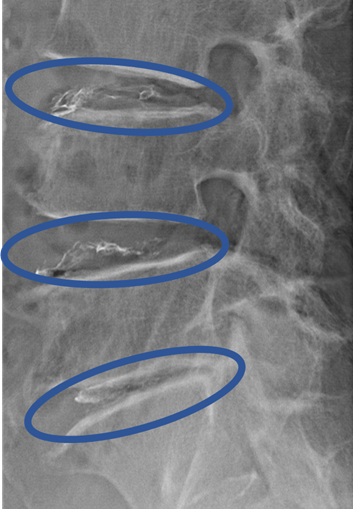

DiscoGelを入れた後の画像になります。

治療は 40分程度で終了

回復室で休憩後、歩いて帰院されました。